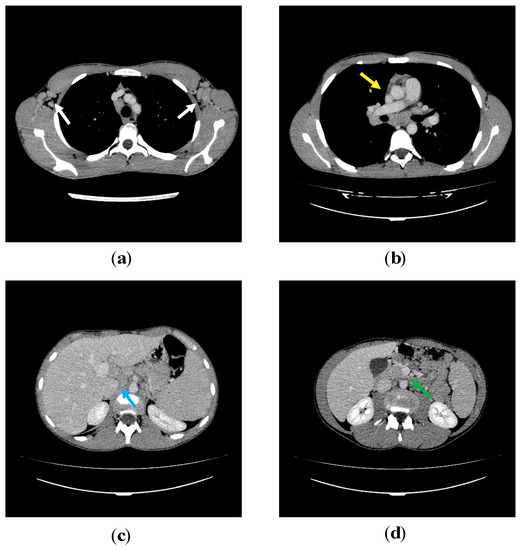

3.3. Lymphoproliferation in APDS-1 Patients